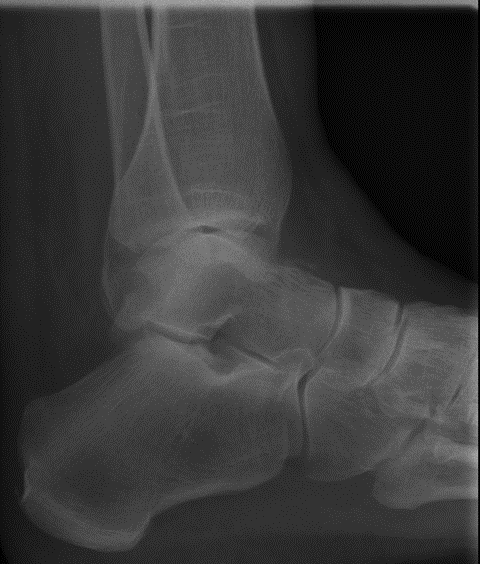

Die Röntgenuntersuchung ergab keinen pathologischen Befund. (Abb.1 und 2)

Abb.1 Unfallbild a.p.

Abb.2 Unfallbild seitlich

Der Bruch des Sprungbeines war auf den nach dem Unfall angefertigten Röntgenbildern nicht erkennbar und wurde erst bei der MRT/CT Untersuchung 9 bzw. 11 Wochen nach dem Unfallereignis festgestellt.